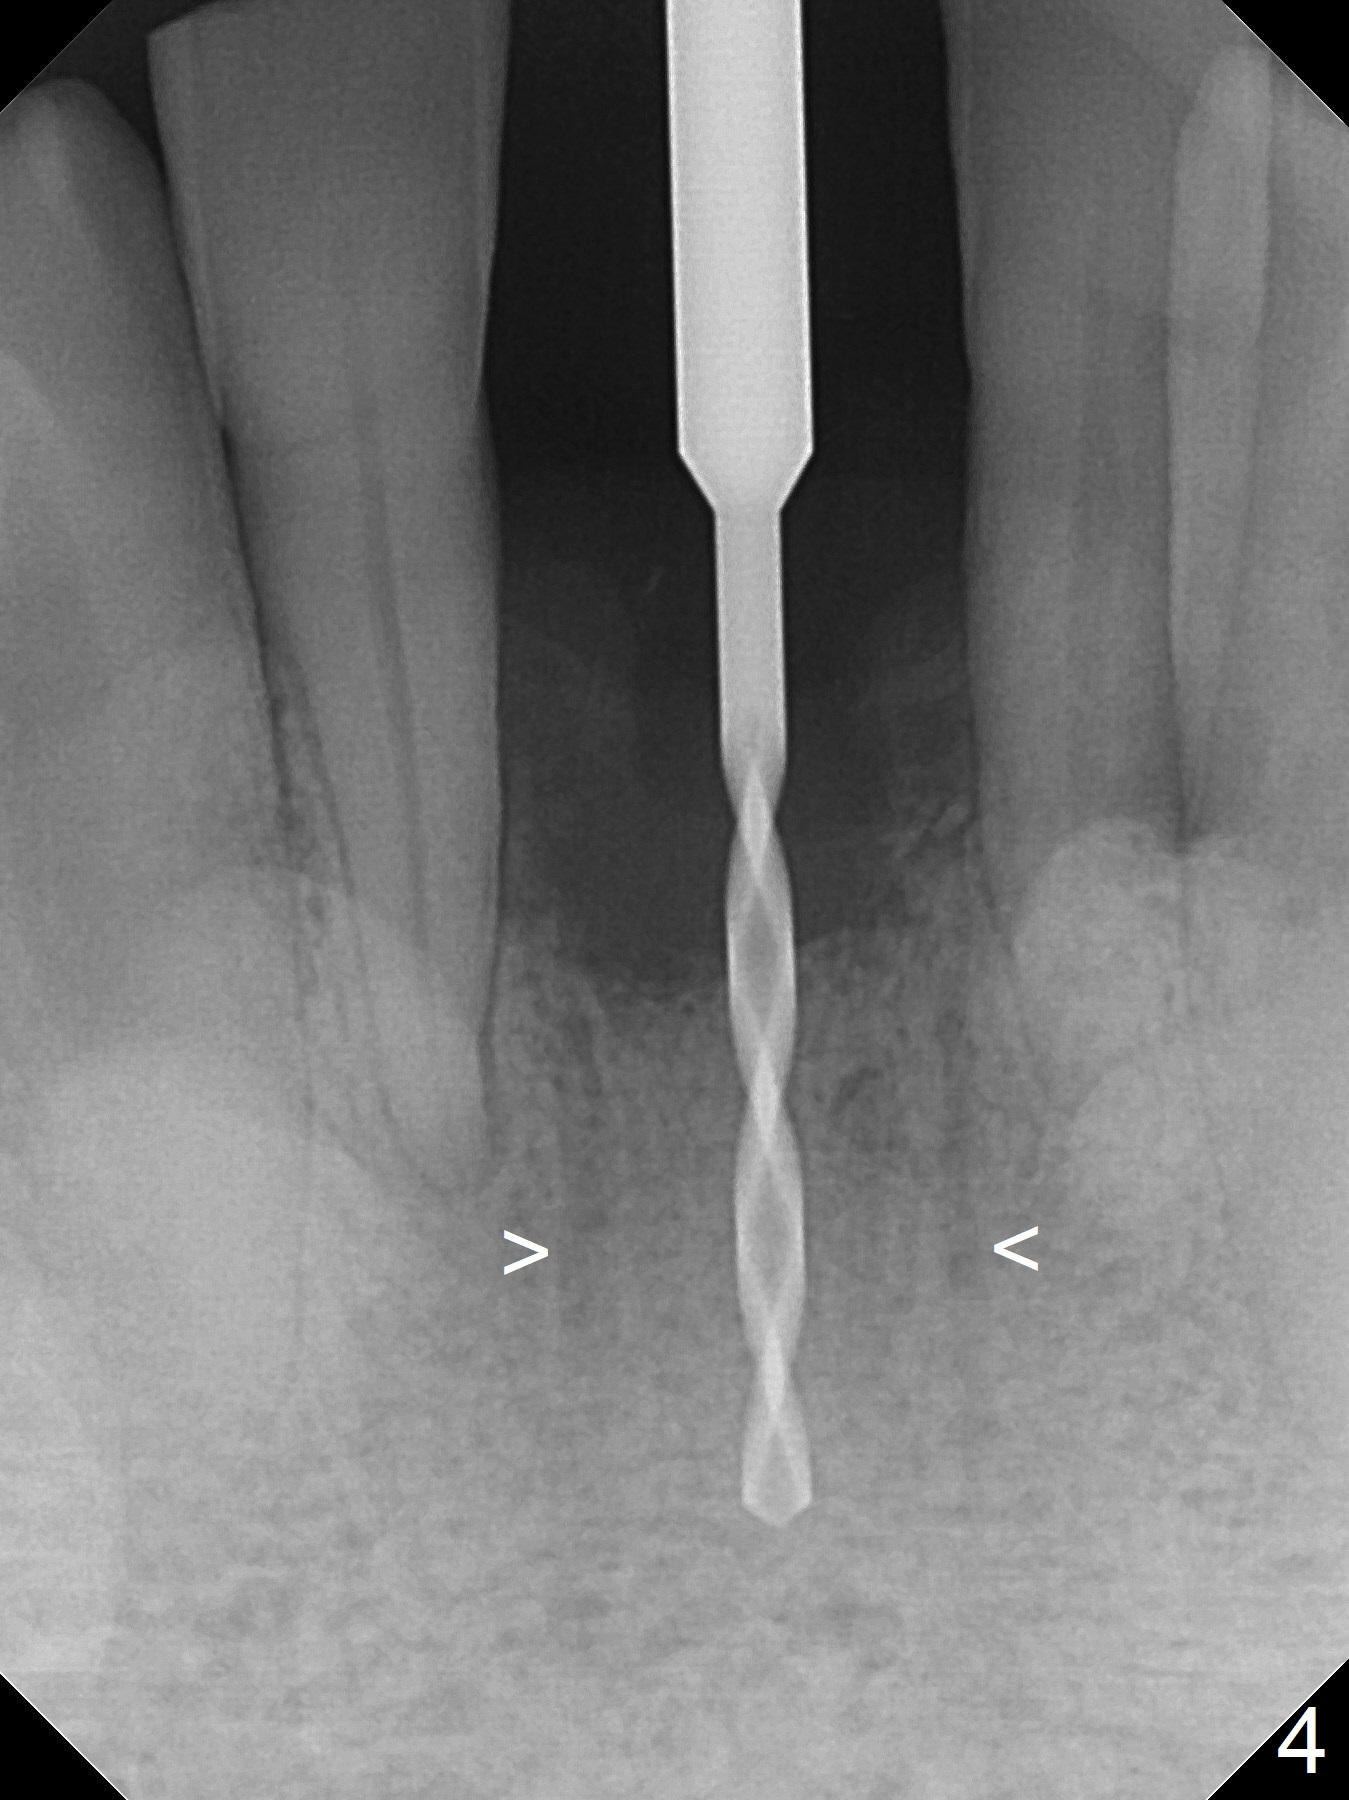

When the patient returns for implant placement 1.5 years after the last treatment (SRP), the tooth #25 has exfoliated, whereas the tooth #24 is severely displaced (Fig.1-3).  In fact the buccolingual plates are found to be lost after extraction, corresponding to change in gingival color indicated by an arrowhead in Fig.1.  Initial osteotomy with 1.2 mm drill is parallel to the terminal branches of the Incisive Canal (Fig.4 arrowheads).  Since the gingiva is as thick as 7.5 mm (Fig.3 arrow), a 3x14 mm 1-piece implant with 4 mm cuff is placed (Fig.5); three implant threads are outside the native bone; with allograft (*) placed and the neighboring crests being coronal to the threads, the chance of periimplantitis should be remote.  An immediate provisional is fabricated to contain the graft in place.  Meanwhile the tooth #2 is symptomatic with crack.  The top 3 threads appear to be contacted by the newly formed crestal bone 6 months postop (Fig.6 *).  Bone appears to have grown into the space between implant threads 6 months post cementation (13 months postop).